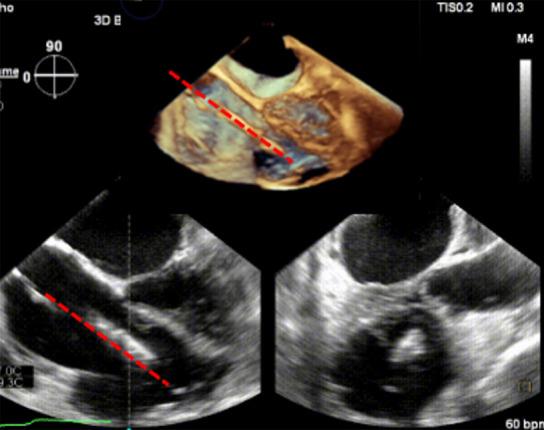

The prohibitive risk of isolated tricuspid valve (TV) surgery encouraged rapid development of a transcatheter solution for tricuspid regurgitation (TR). The favorable results of these devices informed recent guidelines to recommend considering transcatheter treatment of symptomatic secondary severe TR in inoperable patients. Transcatheter TV repair systems usually reduce TR through leaflet approximation and direct annuloplasty. Orthotopic transcatheter TV replacement (TTVR) devices generally rely on radial force and tricuspid leaflet engagement for implantation and stability. The LuX-Valve is a novel radial force-independent orthotopic TTVR device that is operated through the trans-atrial approach. Its radial force-independency is achieved through an interventricular septal anchor tab (septal insertion) and two leaflet graspers (leaflet engagement). Such a unique design makes the intraprocedural imaging different from that of other currently available TTVR systems. The latest generation of this device, the LuX-Valve Plus, comes with a newly designed delivery system through the transjugular approach, which makes the intraprocedural monitoring and adjustment of the device even more complex for successful implantation. However, its unique imaging needs for intra-procedural guidance and post-operative evaluation have not been described before. Therefore, we aimed to elaborate the key steps of transesophageal echocardiography (TEE) to guide this novel procedure. Herein, the primary 2-dimensional (2D) and 3-dimensional (3D) echocardiographic work planes are proposed and the critical steps are emphasized for better communication between imagers and interventionists. The suitability of 2D and 3D echocardiography to guide this procedure is also discussed to increase the flexibility of choice during the implantation.

单纯三尖瓣手术的高风险促使经导管治疗三尖瓣反流(TR)的方法迅速发展。这些装置取得的良好效果为近期的指南提供了依据,指南建议考虑对无法进行手术的有症状继发性重度TR患者进行经导管治疗。经导管三尖瓣修复系统通常通过瓣叶贴合和直接瓣环成形术来减少TR。原位经导管三尖瓣置换(TTVR)装置一般依靠径向力和三尖瓣瓣叶接合来实现植入和稳定。LuX-Valve是一种新型的不依赖径向力的原位TTVR装置,通过经心房途径操作。其不依赖径向力是通过一个室间隔锚定片(间隔插入)和两个瓣叶抓取器(瓣叶接合)来实现的。这种独特的设计使得术中成像与目前其他可用的TTVR系统不同。该装置的最新一代产品LuX-Valve Plus配备了一种新设计的经颈静脉途径输送系统,这使得术中对装置的监测和调整对于成功植入来说更加复杂。然而,其在术中引导和术后评估方面独特的成像需求此前尚未有描述。因此,我们旨在详细阐述经食管超声心动图(TEE)引导这一新型手术的关键步骤。在此,我们提出了主要的二维(2D)和三维(3D)超声心动图工作平面,并强调了关键步骤,以便成像人员和介入医生之间能更好地沟通。还讨论了二维和三维超声心动图引导该手术的适用性,以增加植入过程中选择的灵活性。